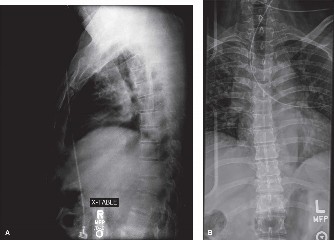

Expected surgical outcomes following revision surgery for recurrent disc herniation? CASE 3 A 27-year-old previously healthy woman is transferred directly to your trauma center with severe low back pain after jumping from an overpass in an apparent suicide attempt. The trauma team completes the primary survey, and the patient is hemodynamically stabilized with fluid resuscitation. On secondary survey she is found to have significant pain with examination/manipulation of her pelvis. Lower extremity examination demonstrates multiple superficial abrasions and grade 4/5 strength with great toe extension and ankle dorsiflexion on the left. Inspection of the perineum shows no blood at the urethral meatus or rectum; however, rectal tone and perianal sensation are decreased. The remainder of the examination is unremarkable. An anteroposterior view of the pelvis demonstrates unilateral superior and inferior rami fractures and a right L5 transverse process fracture.

The correct answer is (C). It is important to recognize that plain radiographs may only detect 30% of sacral injuries. This patient’s plain x-ray findings are highly suggestive of more substantial injuries than isolated rami fractures and transverse process fractures. In fact, the transverse process fracture should be assumed to have occurred by avulsion via the lumbosacral ligaments, which suggests large displacement of the hemipelvis. While plain radiographs may demonstrate sagittal displacement of sacral fractures, they are often of poor quality and do not enable

delineation of the entire fracture pattern. A pelvic computed tomography (CT) scan is indicated to better evaluate the bony injury as well as canal encroachment, particularly in the setting of a neurological deficit. An angiogram might be indicated if the patient was hemodynamically unstable and an intrapelvic bleed was suspected. CT scan images of the above patient are shown inFigures 1–8 and 1–9. Definitive management of this injury should be: 1. 3 months of bed rest followed by progressive mobilization

Figure 1–8 Mid-sagittal image of the pelvis.

Figure 1–9 Axial image of the pelvis.

The correct answer is (D). Critical steps in decision-making include determination of neurologic status, presence of associated pelvic ring injuries, and stability of the lumbopelvic junction. The neurologic examination demonstrates a deficit that is at least in part localized to the sacral nerve roots. In the presence of sacral canal compromise, decompression via laminectomy is indicated. The CT scan demonstrates a U-type injury with a high transverse sacral fracture and bilateral vertical extension through the sacral foramen. In the descriptive classification of sacral fractures in Denis zone 3, H-type and U-type sacral fractures represent spinopelvic dissociation and must be distinguished from fractures localized to the posterior pelvic ring, which are vertically unstable. The spinopelvic junction serves as a critical transitional zone as the axial load of the upper body is distributed from the upper sacrum to the ilium and finally the acetabulum. Surgery is indicated to prevent progressive deformity and chronic pain. Reconstruction should include stabilization from the lumbar spine to the pelvis using a pedicle screw/iliac screw construct. Nonoperative treatment with progressive mobilization is not appropriate for this type of fracture. Plating of the sacrum is not sufficient to restore stability of this injury; nor are sacroiliac screws.